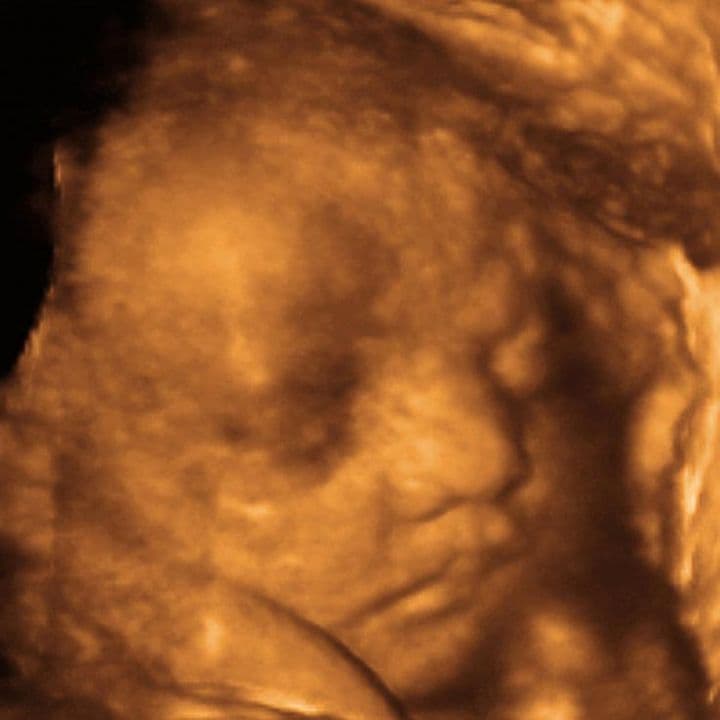

35 weeks and 5 days pregnant

Many babies will still have a good volume of amniotic fluid around them, but shadows from the placenta or side of the uterus, coupled with the curled up fetal position, will make imaging the baby harder and harder.